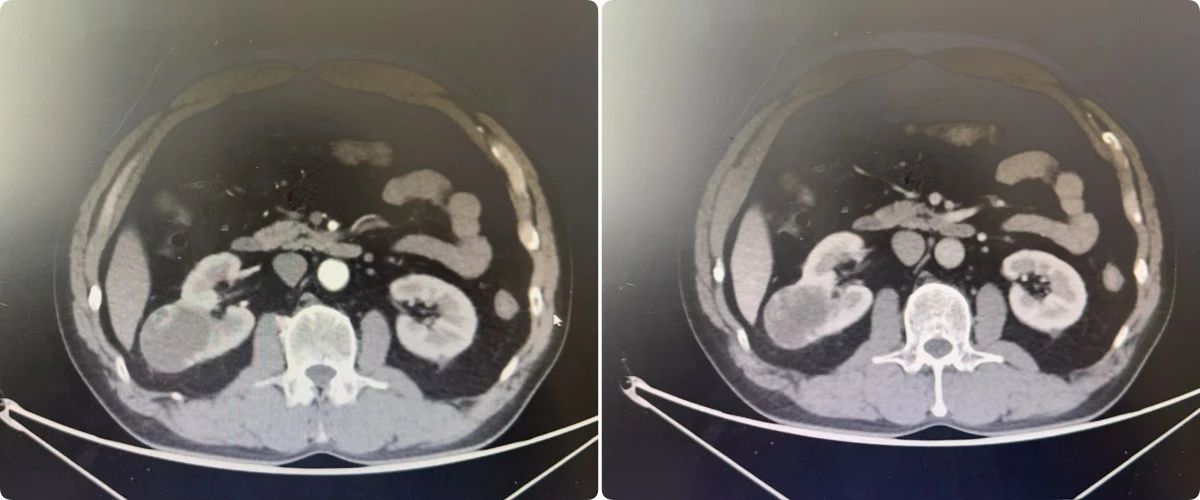

病例1:一位因排尿困难就诊的患者,在细致检查后被确诊为右肾占位性病变(倾向恶性),并伴有前列腺增生。面对复杂病情,我院泌尿外科团队在充分术前评估与多学科会诊的基础上,精心制定了分阶段治疗方案。首先解决患者排尿难题,随后择期实施了腹腔镜下肾根治性切除术,实现了对病灶的精准切除。患者术后恢复良好,生活质量得到提升。病例2:患者因右侧肾盂结石反复泌尿道感染,经抗炎治疗效果不佳。泌尿外科团队决定采用经尿道输尿管软镜肾盂激光碎石取石术,手术成功,感染得到控制。病例3:患者因“尿频、夜尿增多”来院拟行前列腺手术。入院进一步CT检查发现左肾肿瘤、考虑恶性。团队经充分评估,行腹腔镜下肾根治性切除术。病例4:一例无痛性肉眼血尿患者,经增强CT确诊输尿管占位性病变后,行腹腔镜下左侧肾输尿管全长及部分膀胱切除术。腹腔镜下肾切除术有什么优势呢?